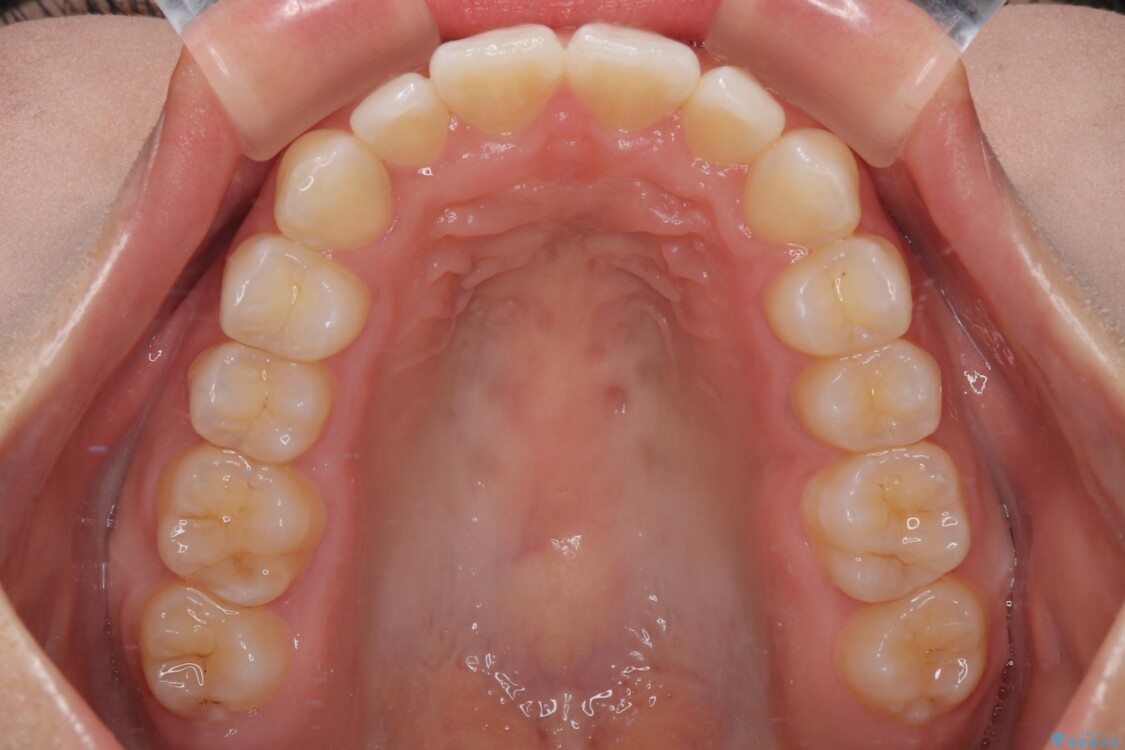

治療前

• 目立ちにくい表側装置で1年完了!狭いアーチを側方拡大し前歯のデコボコを整えた症例 治療前画像